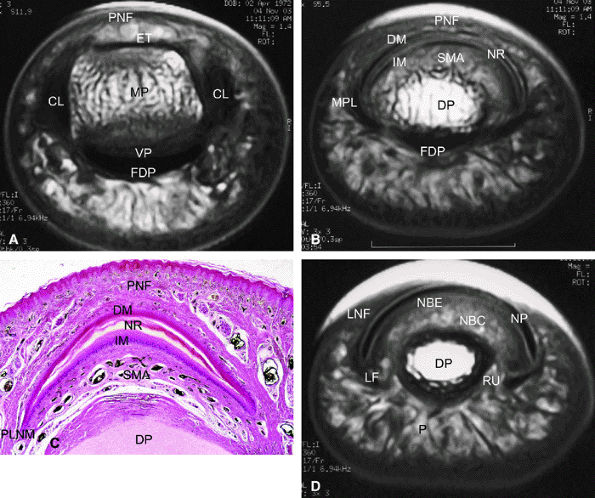

FIGURE 11.104 ● Sagittal anatomy of the nail unit. (A) T1-weighted image showing the surface of the nail plate (arrows) highlighted by petroleum jelly deposits. (B) Dorsal oblique view of the nail unit: 1, nail plate; 2, onychodermal band; 3, free edge of plate; 4, lunula; 5, cuticle; 6, proximal nail fold; 7, inferior aspect of proximal nail fold or eponychium; 8, proximal or dorsal nail matrix; 9, cul-de-sac; 10, intermediate or ventral nail matrix; 11, nail bed epithelium ridges; 12, nail bed corium; 13, hyponychium; 14, distal groove; 15, matrix phalangeal ligament; 16, submatrical hypersignal area; 17, network of collagenous fibers; 18, hyponychio-phalangeal ligament; 19, glomus body; 20, proximal dorsal arterial arch; 21, distal dorsal arterial arch; 22, distal matrix arterial arch; 23, nail bed arterial arch; 24, middle phalanx; 25, distal interphalangeal joint; 26, volar plate; 27, distal phalanx; 28, tuberosity of distal phalanx; 29, flexor digitorum profundus tendon; 30, terminal band of extensor tendon; 31, pulp.

FIGURE 11.105 ● Photomicrograph of nail matrix in sagittal section with hematoxylin and eosin staining. PNF, proximal nail fold; EE, epithelium eponychium; C, cuticle; DM, dorsal matrix; IM, intermediate matrix; NBE, nail bed epithelium; CDS; matrix cul-de-sac; NP, nail plate; DP, distal phalanx.

FIGURE 11.108 ● Axial anatomy of the nail unit. (A) Distal interphalangeal joint. (B) Matrix area. (C) Photomicrograph of the matrix area with hematoxylin and eosin staining. (D) Nail bed area. ET, extensor tendon; PNE, posterior nail fold; CL, collateral ligament; MP, middle phalanx; VP, volar plate; FDP, flexor digitorum tendon; MPL; matricophalangeal ligament; NR, nail root; PLNM, posterolateral corners of the nail matrix; SMA; submatrix area; DM; dorsal matrix; IM, intermediate matrix; DP, distal phalanx; P, pulp; LF, ligament of Flint; NBE, nail bed epithelium; NBC, nail bed corium; LNF, lateral nail fold; RU; rima ungualum.